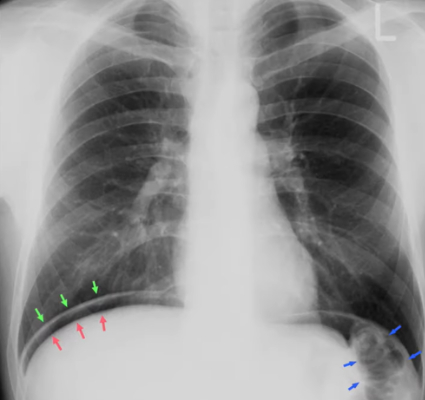

To what structure are the arrows pointing?

B) Inner and outer layers of the intestine